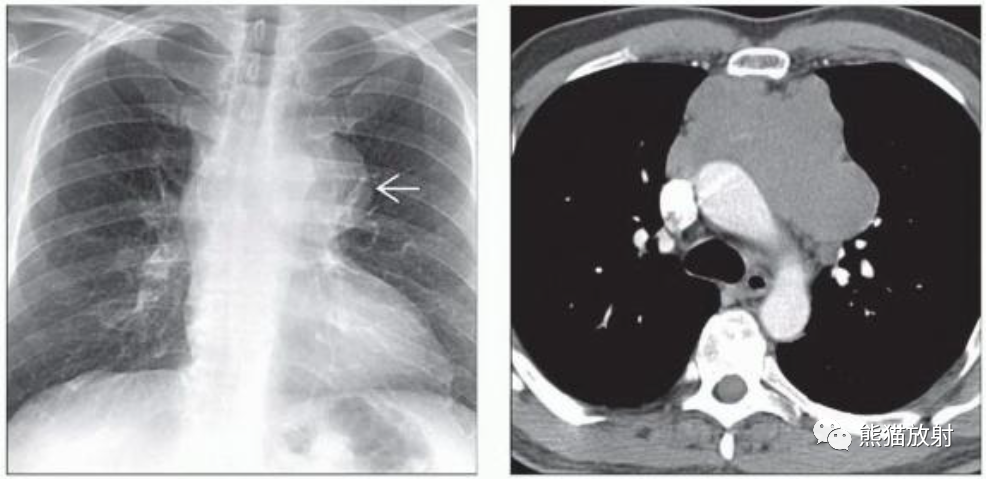

(左)中年男性,胸痛。PA胸片显示左前纵隔分叶状肿块。主动脉弓边缘可见。

(右)同一患者,轴位CECT显示前纵隔分叶状肿块延伸至中线两侧,病变轻微强化。纵隔精原细胞瘤可能类似于纵隔HL和NHL的淋巴结融合。